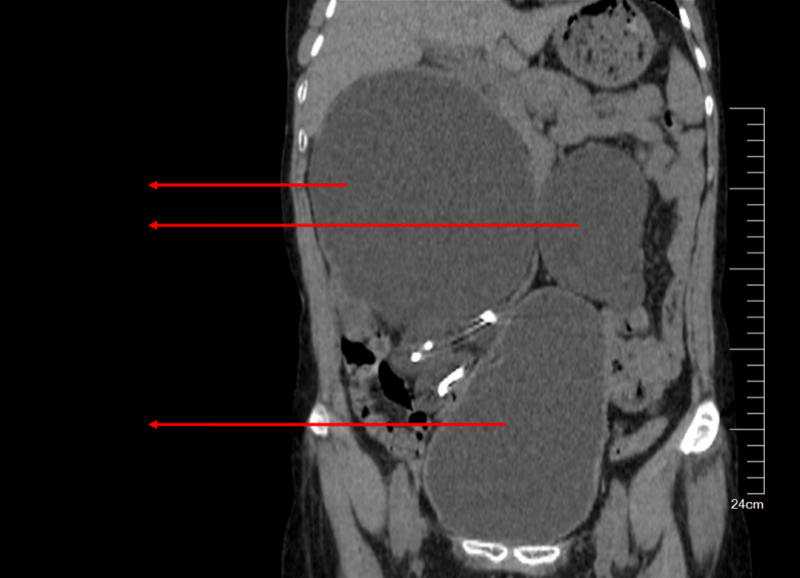

双肾重度积水 , 出现“水滴型”大膀胱

接诊的泌尿外科主任古迪仔细询问了冯姐既往的患病史、具体症状、相关的治疗情况 , 经尿路CT检查显示 , 患者双肾重度积水 , 膀胱明显增大像“水滴型” , 明确诊断为这是由于膀胱肌肉受到破坏 , 逼尿肌无力收缩引起的病症 。

古迪主任说 , 由于尿不能从下面排出去 , 肾脏产生的尿液就被憋在体内 , 才导致了肾脏严重积液、膀胱明显增大 , 因而肾脏功能受到损害 , 导致发生尿毒症、休克等严重并发症 , “她的膀胱肌肉不断受到损害 , 尿液更难排出去 , 形成恶性循环 。 ”